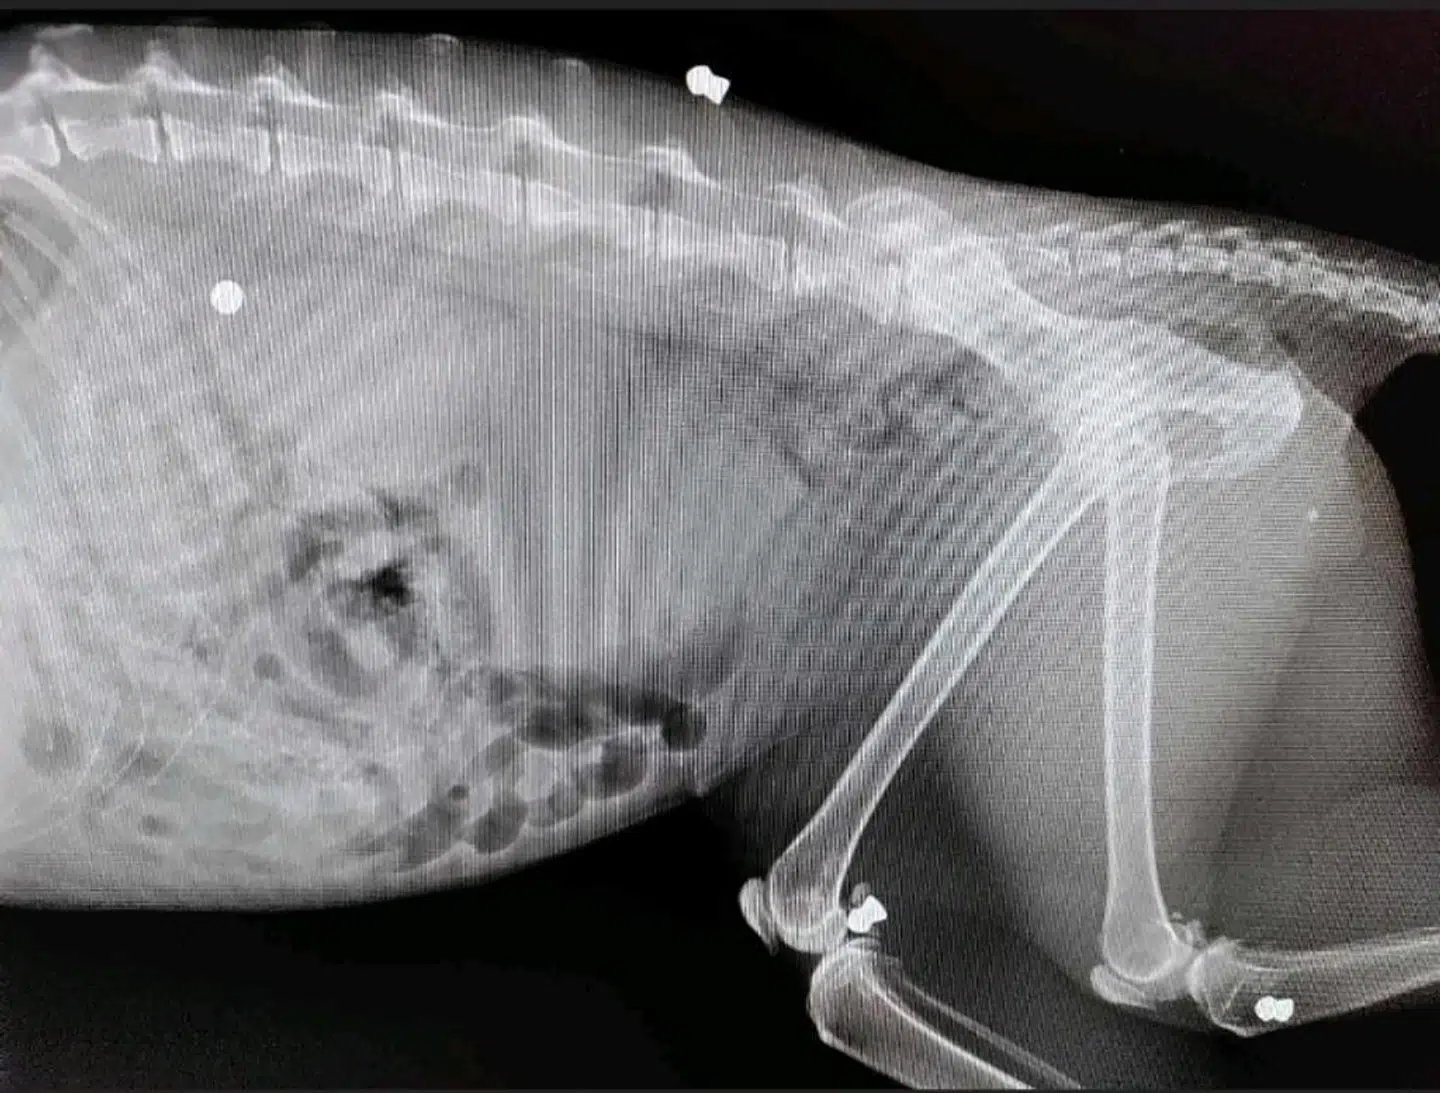

Den anden, 'Bluey', blev skudt i maven og ankom 'stærkt blødende og med store smerter' til en dyreklinik.